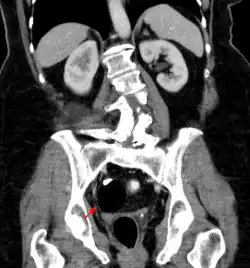

Diagnosis

Teratomas are thought to originate in utero, so can be considered congenital tumors. Many teratomas are not diagnosed until much later in childhood or in adulthood. Large tumors are more likely to be diagnosed early on. Sacrococcygeal and cervical teratomas are often detected by prenatal ultrasound. Additional diagnostic methods may include prenatal magnetic resonance imaging. In rare circumstances, the tumor is so large that the fetus may be damaged or die. In the case of large sacrococcygeal teratomas, a significant portion of the fetus' blood flow is redirected toward the teratoma (a phenomenon called steal syndrome), causing heart failure, or hydrops, of the fetus. In certain cases, fetal surgery may be indicated.

Beyond the newborn period, symptoms of a teratoma depend on its location and organ of origin. Ovarian teratomas often present with abdominal or pelvic pain, caused by torsion of the ovary or irritation of its ligaments. A recently discovered condition where ovarian teratomas cause encephalitis associated with antibodies against the N-methyl-D-aspartate receptor antibody (NMDAR) - often referred to as "anti-NMDA receptor encephalitis", was identified as a serious complication. Patients develop a multistage illness that progresses from psychosis, memory deficits, seizures, and language disintegration into a state of unresponsiveness with catatonic features often associated with abnormal movements, and autonomic and breathing instability.[34] Testicular teratomas present as a palpable mass in the testis; mediastinal teratomas often cause compression of the lungs or the airways and may present with chest pain and/or respiratory symptoms.

Adequate follow-up requires close observation, involving repeated physical examination, scanning (ultrasound, MRI, or CT), and measurement of AFP and/or βhCG.[54][55]